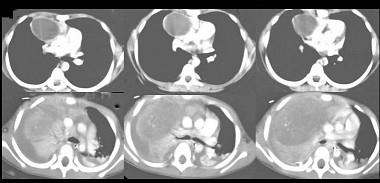

问题 14岁,男,胸闷咳嗽1个月,曾咳出过毛发,CT检查如图,请选择最可能的诊断 ( )

选项 A.纵隔血肿 B.胸内甲状腺肿 C.胸腺囊肿 D.畸胎瘤 E.食管囊肿

答案 D